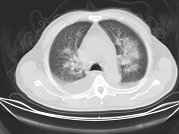

- 单项选择题男,32岁, CT图像如图,最可能的诊断为 ( )

A、肺水肿并双侧胸腔积液

B、周围型肺癌

C、肺动静脉瘘

D、肺错构瘤

E、炎性假瘤